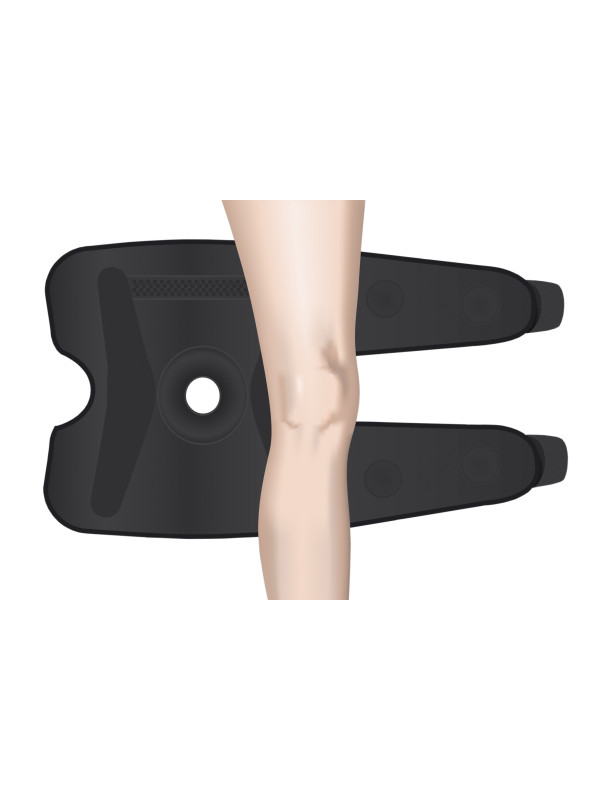

Orteza kolana 7120 została zaprojektowana z wykorzystaniem trzywarstwowej konstrukcji, składającej się z elastycznego materiału z mikrofibry na zewnątrz, warstwy pianki poliuretanowej w środku oraz miękkiego materiału frotte wewnętrznie. Ta innowacyjna konstrukcja charakteryzuje się doskonałym dopasowaniem i przyleganiem do kolana. Dodatkowo, wewnętrzną stronę ortezy wyposażono w silikonowy bąbelkowy pas antypoślizgowy, aby zapewnić lepszą przyczepność.

W celu zwiększenia komfortu użytkowania, orteza posiada otwór okołorzepkowy z ukrytym pierścieniem silikonowym, który wykonuje micromasaż podczas ruchu stawu. Działa to nie tylko stabilizująco, ale także stymuluje mikrokrążenie krwi w okolicy kolana.

Dodatkowo, orteza wyposażona jest w boczne, ukryte szyny stabilizujące, umożliwiające regulację kąta zgięcia (0, 30, 60 i 90 stopni). Te szyny dostarczają podparcia i stabilizacji, szczególnie w obszarze boczno-przyśrodkowym stawu, co przyczynia się do skutecznej rehabilitacji.

Aby kompleksowo zabezpieczyć kończynę, zastosowano także owijane dookoła taśmy stabilizacyjne na udzie i podudziu. Działają one synergistycznie z pozostałymi elementami ortezy, tworząc solidną ochronę, przy jednoczesnym zachowaniu komfortu noszenia.